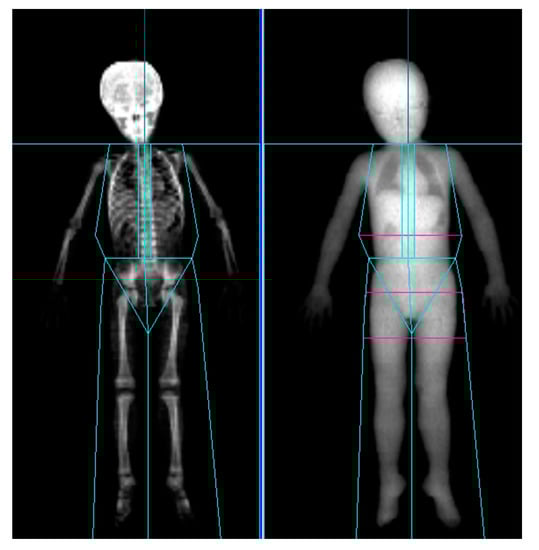

LBM was measured by DXA preinjection as well as at 4 and 12 weeks after injection. At each acquisition, LBM of the affected leg, unaffected leg, and both upper limbs were collected. All participants were scanned using GE Healthcare Prodigy densitometers (GE Healthcare, Madison, WI, USA) in a routine clinical manner, in accordance with the manufacturer’s recommendations. For Prodigy, Encore version 14.1 software (GE Healthcare) was used for the analysis and acquisition (Figure 2). As anatomical landmarks of the arms and legs, lines perpendicular to the axis of the femoral neck and angled with the pelvic brim and center of the arm socket were drawn. Soft tissue extending from the femoral neck to the toes and from the humeral head to the fingertips were included [25,30].

Figure 2.

Dual-energy X-ray absorptiometry scan of a 4-year-old cerebral palsy patient showing positions of regional markers.